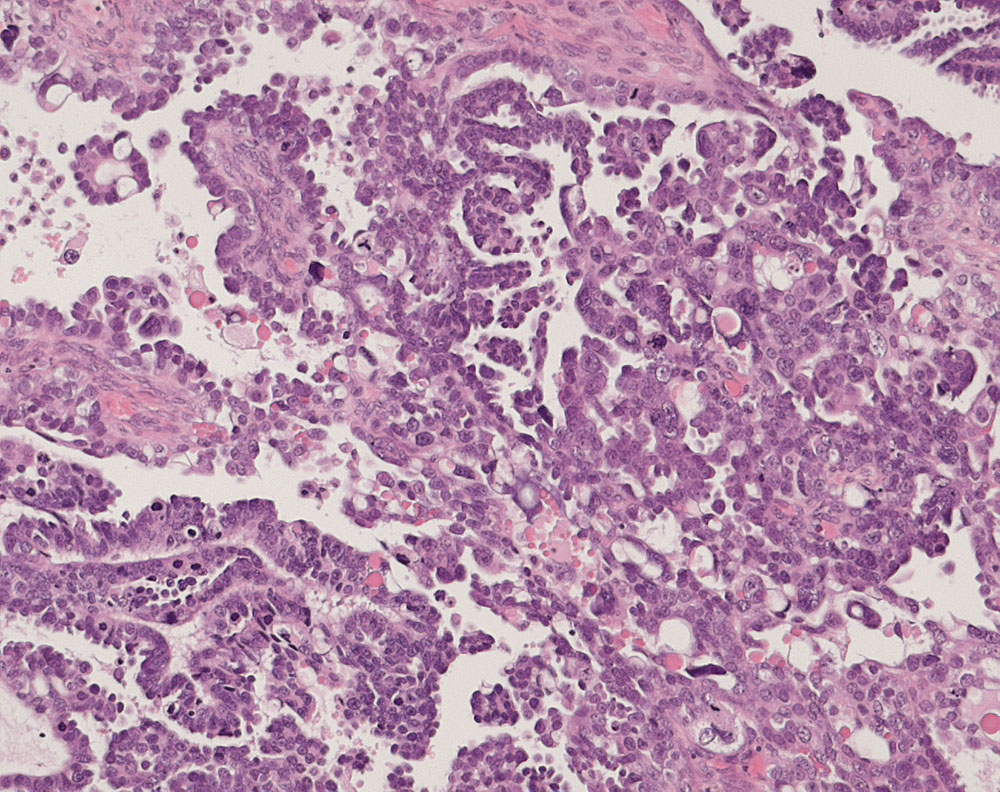

PathoPic – image database / PathoPic ID 10934 - seröses Ovarialkarzinom high grade

seröses Ovarialkarzinom high grade

Papillärer Tumor bestehend aus stark atypischen und vereinzelt bizarren pleomorphen Tumorzellen mit starken Kerngrössenschwankungen. Mehrere, teils atypische Mitosen und Apoptosen.

Verdacht auf Ovarialkarzinom (CA125 > 2000u/l). CT: Vergrösserte Ovarian beidseits. Maligner Pleuraerguss Adenokarzinom.